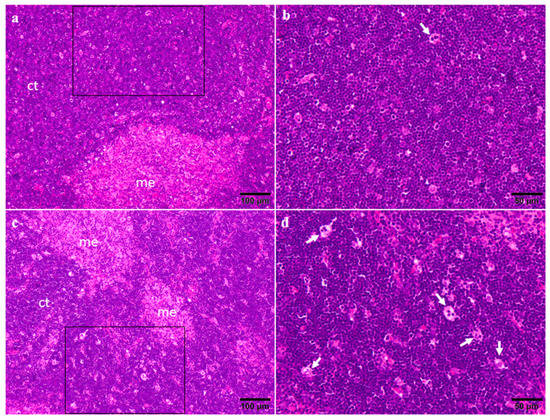

2.3. Organ Weights and Histopathology